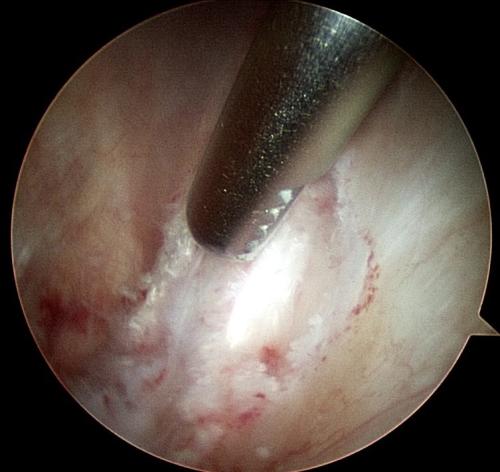

A rehabilitation program will be provided for your horse. This may also include suggestions for post-surgical treatments. For example, it is routine to perform Hyaluronic acid/corticosteroid injections at 2 weeks post surgery following arthroscopic chip/fragment removal. When there is substantial soft-tissue or cartilage injury, we often recommend biologic therapies.